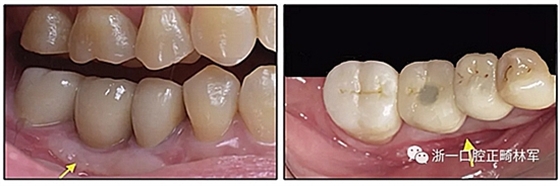

圖17. 在高于頰側(cè)前庭區(qū)域,下頜右側(cè)種植體支持的修復(fù)體(右側(cè)第一磨牙區(qū)域)的頸部上存在較深的凹面。另外,僅有0.5mm寬的角化牙齦。 盡管組織是健康的,但凹陷的鄰近區(qū)域?qū)颊邅?lái)說(shuō)十分容易引起食物嵌塞。

圖19. 在術(shù)后愈合期后,游離齦瓣增加了附著組織的寬度(左箭頭),并矯正了咀嚼時(shí)食物向頰側(cè)的問(wèn)題(右箭頭)